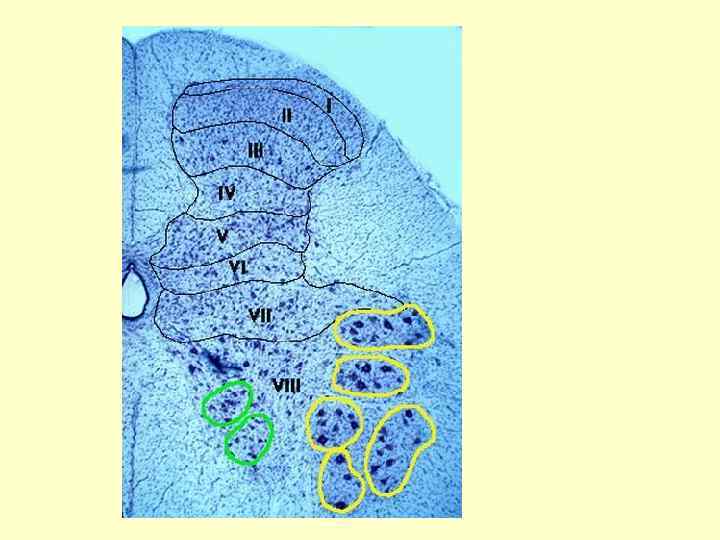

Строение и функции серого вещества спинного мозга. Пластины Рекседа. Деление серого вещества по цитоархетиктоническому принципу (в основе строение нейронов)

Строение и функции серого вещества спинного мозга. Пластины Рекседа. Пластина Состав и функции I Маргинальная зона. Тонкий слой сенсорных нейронов, получающий информацию от рецепторов, чувствительных к боли и холоду II, III Желетинозная субстанция Роланда. Содержит маленькие вставочные интернейроны, которые модулируют сенсорные сигналы (выделяет субстанцию Р) от болевых и холодовых рецепторов IV Сенсорные нейроны, получающие входы периферических рецепторов, отвечающих на раздражение различных модальностей (мультимодальные нейроны). Аксоны этих нейронов составляют восходящие спино-цервикальный (к шейному ядру) и спино-таламический тракты V VI Интернейроны, получающие как нисходящую информацию от коры головного мозга и других сегментов спинного мозга, так и сенсорную от проприоцепторов туловища и конечностей.

Строение и функции серого вещества спинного мозга. Пластины Рекседа. 2. Пластина Состав и функции VII Ядро Кларка содержит переключательные нейроны второго порядка для проприоцептивной сенсорной информации от нижних конечностей, внутренее медиальное ядро (боковой рог) содержит преганглионарные нейроны вегетативной НС (передают нисходящую информацию от вышележащих отделов ЦНС к вегетативной НС) VIII Передний рог содержит интернейроны участвующие в контроле движений, связаны с медиальными моторными нейронами следующей пластины IX Мотонейроны (альфа- и гамма-), иннервирующие мускулатуру туловища (вентромедиальная часть) и конечностей (дорзолатеральная) X Область вокруг спинномозгового канала содержит мелкие нейроны, принимающие участие в обработке информации от болевых, висцеральных и температурных рецепторов; немиелинизированные коммисуральные (перекрещивающиеся) волокна